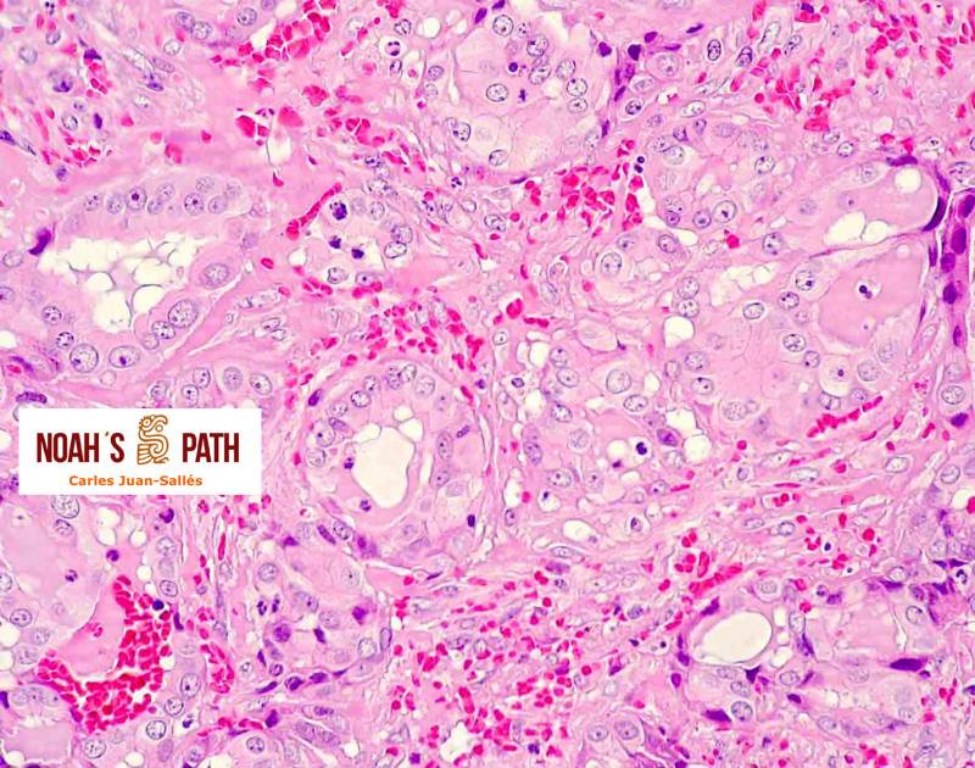

Coriocarcinoma uterino no gestacional

Chinchilla